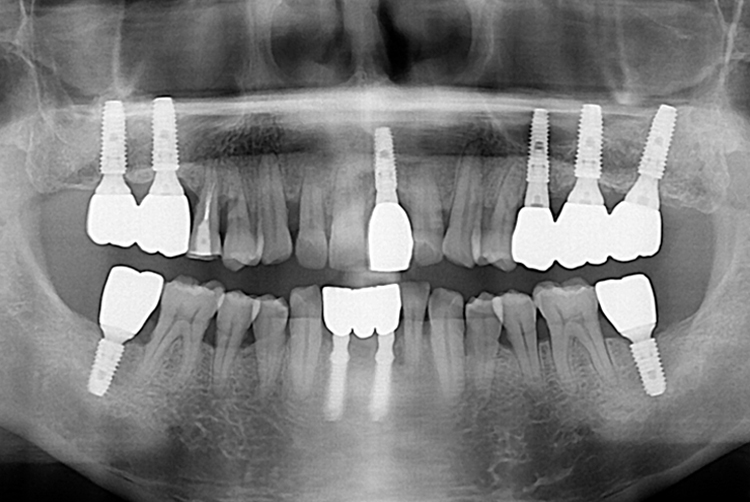

1500 조현욱_후.jpg

치료후 : 2019-08-22

세종치과는 많은 환자와 다양한 케이스를 바탕으로 항상 편안한 임플란트 수술을 제공하고자 노력하고,

오래동안 튼튼히 쓸 수 있는 임플란트 수술을 가장 큰 목표로 삼고 있습니다